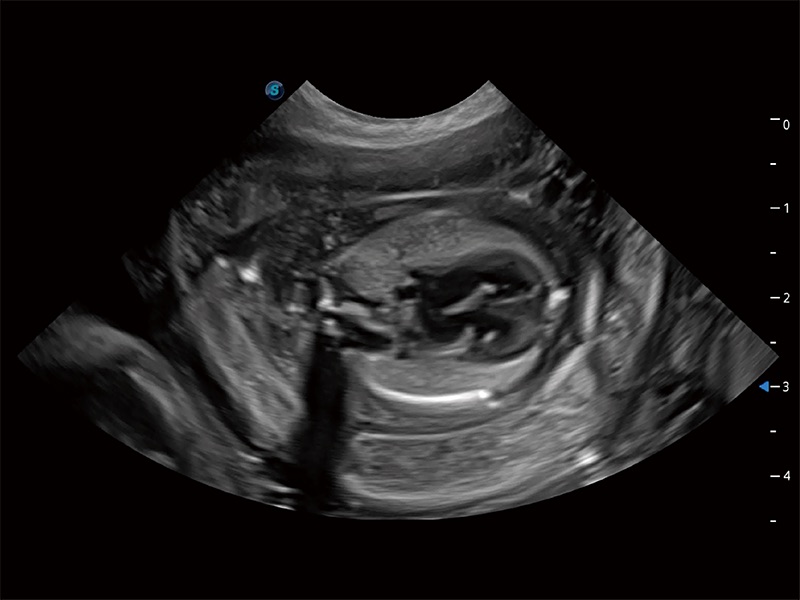

动物是人类最亲密的朋友和最值得信赖的伙伴。狗万官方网站也一直致力于探索动物专用的超声影像解决方案。全新推出的ProPet系列,是狗万官方网站在动物超声影像智能化、专业化、精准化的一次跨越式革新。动物不能用言语来表述自己的不适,通过超声影像,ProPet系列搭建了动物医生与不同物种沟通的“桥梁”,为动物医生注入了“治愈之力”。 ProPet 80 是狗万官方网站匠心打造的一款高端动物专用彩超,采用性能卓越的全新硬件架构,极大提升超声系统的运行效率和数据处理能力,帮助动物医生从容应对日益增多的挑战性病例和日益多样化的临床需求。

高性能和先进的临床应用工具可以为动物医生提供临床信心。ProPet 80 搭载了先进的腹部和浅表应用工具,帮助医生在日常临床实践中发挥前所未有的作用。

ProPet 80 专为动物医生设计,对不同的动物体型和生理结构作出了针对性的优化。通过动物影像专用软件,可满足个性化的应用需求,帮助动物医生获得更精确的诊断数据。

ProPet 80 全新的动物超声智能软件和丰富的探头群,为动物医生提供了高清晰度和精细分辨率的图像,无论在宠物、马科、畜牧还是实验室动物等应用中都可以轻松应对,为您的日常工作带来满意的体验。